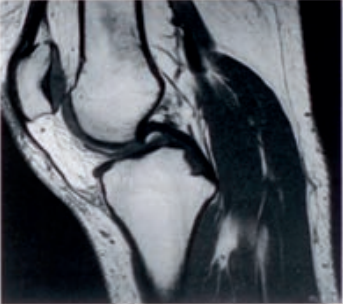

Na rentgenogramie przedstawione jest złamanie Saltera-Harrisa typu

Ilustracja do pytania 2

A. V czwartej kości śródręcza.

B. II odcinka bliższego kości piszczelowej.

C. III nasady dalszej kości piszczelowej.

D. I ześlizgnięcie bliższej nasady kości udowej lewej.